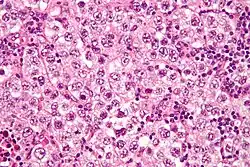

Micrograph of a seminoma, a common germ cell tumor. | |

Germinoma (including dysgerminoma and seminoma) | 40–50 | Malignant | Sheets of uniform polygonal cells with cleared cytoplasm; lymphocytes in the stroma | About 10% have elevated hCG | |